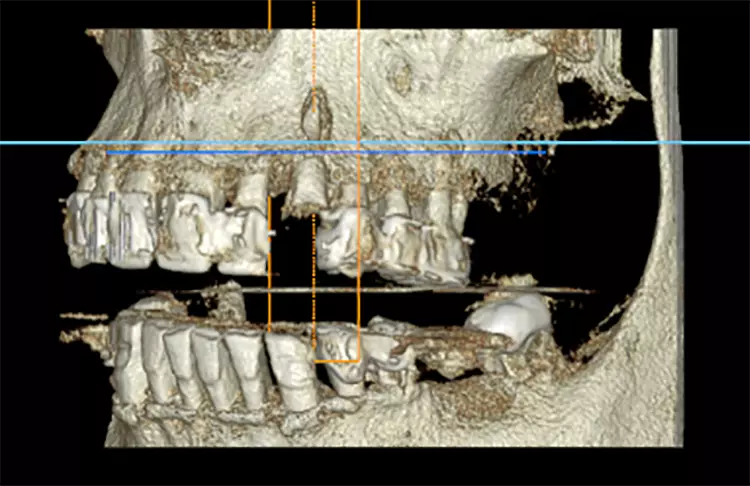

Bei diesem 49-jährigen, allgemeinanamnestisch unauffälligen Patienten liegen diverse ästhetisch störende Zahnstellungsanomalien vor, wobei Zahn 21 bei extremer Elongation frakturierte (Abb. 2a). Nach einer Übergangsversorgung mittels provisorischer Stiftkrone (Abb. 2b) entschied sich der Patient für eine Zahnentfernung bei gleichzeitiger Implantation. Im Ausgangs-DVT (Abb. 2c und d) zeigt sich im Cross-Sectional, wie weit der Processus alveolaris zurückliegt.